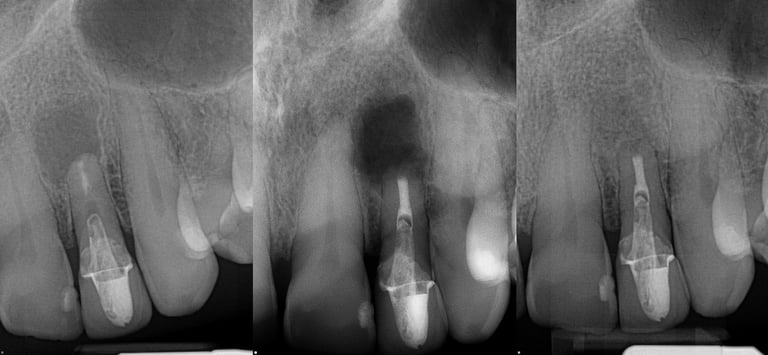

Gallery 2: Retreatment Cases

Retreatment Root Canal Cases with preoperative and postoperative radiographs.

#10 ReTx (original RCT poorly done)